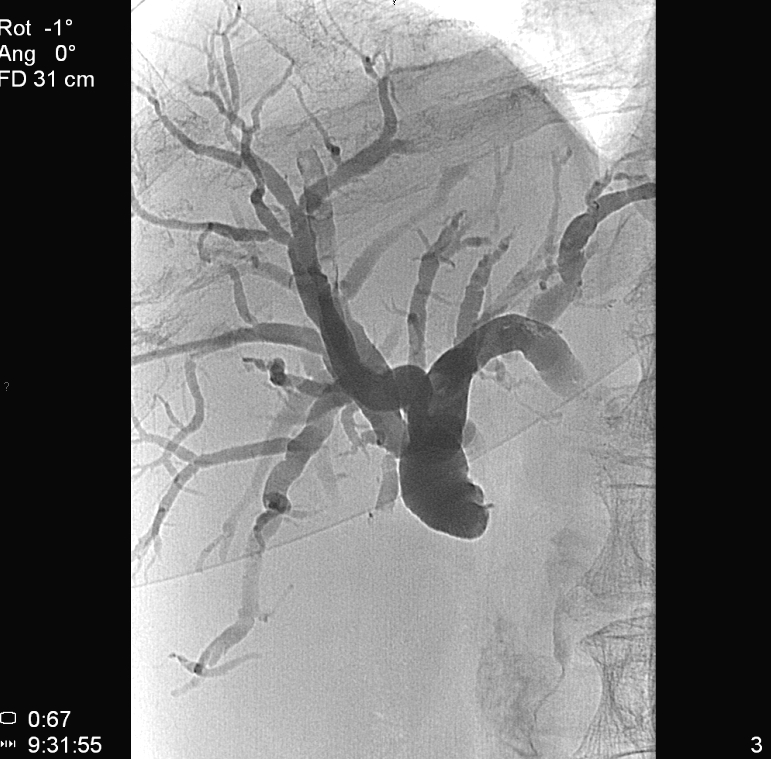

TAE (Transcatheter Arterial Embolization) and TACE (Transcatheter Arterial ChemoEmbolization) are methods with which the supplying artery/arteries of the tumor are selectively approached through the branches of the hepatic artery. When the catheter is in position the tumor branches are injected with a special, oily contrast material, Lipiodol (TAE). The injected material is used as an embolization material (figure 18.), other chemotherapeutical drugs (5-Fluoro-Uracil, Epirubicin, Cisplatin, Mytomicin-C) can also be used (TACE) (figure 19.).

Image

Figure 18. – Lipiodol uptake in HCC, selective catherarization, injection of 10 ml Lipiodol (DSA)

Compared to systemic chemotherapy, with these methods 10 or even 100 times greater drug concentrations can be delivered to the tumor tissue. Moreover, due to the effects of Lipiodol, the drug effects persist longer, while normal liver parenchyma will wash out the chemicals faster leaving little or no harm.

This can be successfully combined with the other percutaneous methods, especially during the treatment of multiplex primary and secondary tumors.